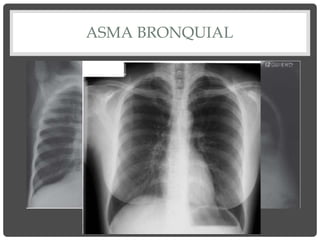

ASMA BRONQUIAL

Signos de atrapamiento aéreo

SIGNOS DE HIPERINSUFLACIÓN •Descenso y aplanamiento de los diafragmas. • Senos costofrénicos tienden a desaparecer. • Aumento de tamaño de los espacios claros retroesternal y retrocardíaco. • Costillas horizontalizadas y espacios intercostales ensanchados. • Columna arqueada: cifosis pronunciada. • Esternón protruido. Tórax en tonel. • Trastornos vasculares: hilios grandes, disminución de la vasculatura periférica, corazón en gota.

ASMA BRONQUIAL Signos deatrapamiento aéreo